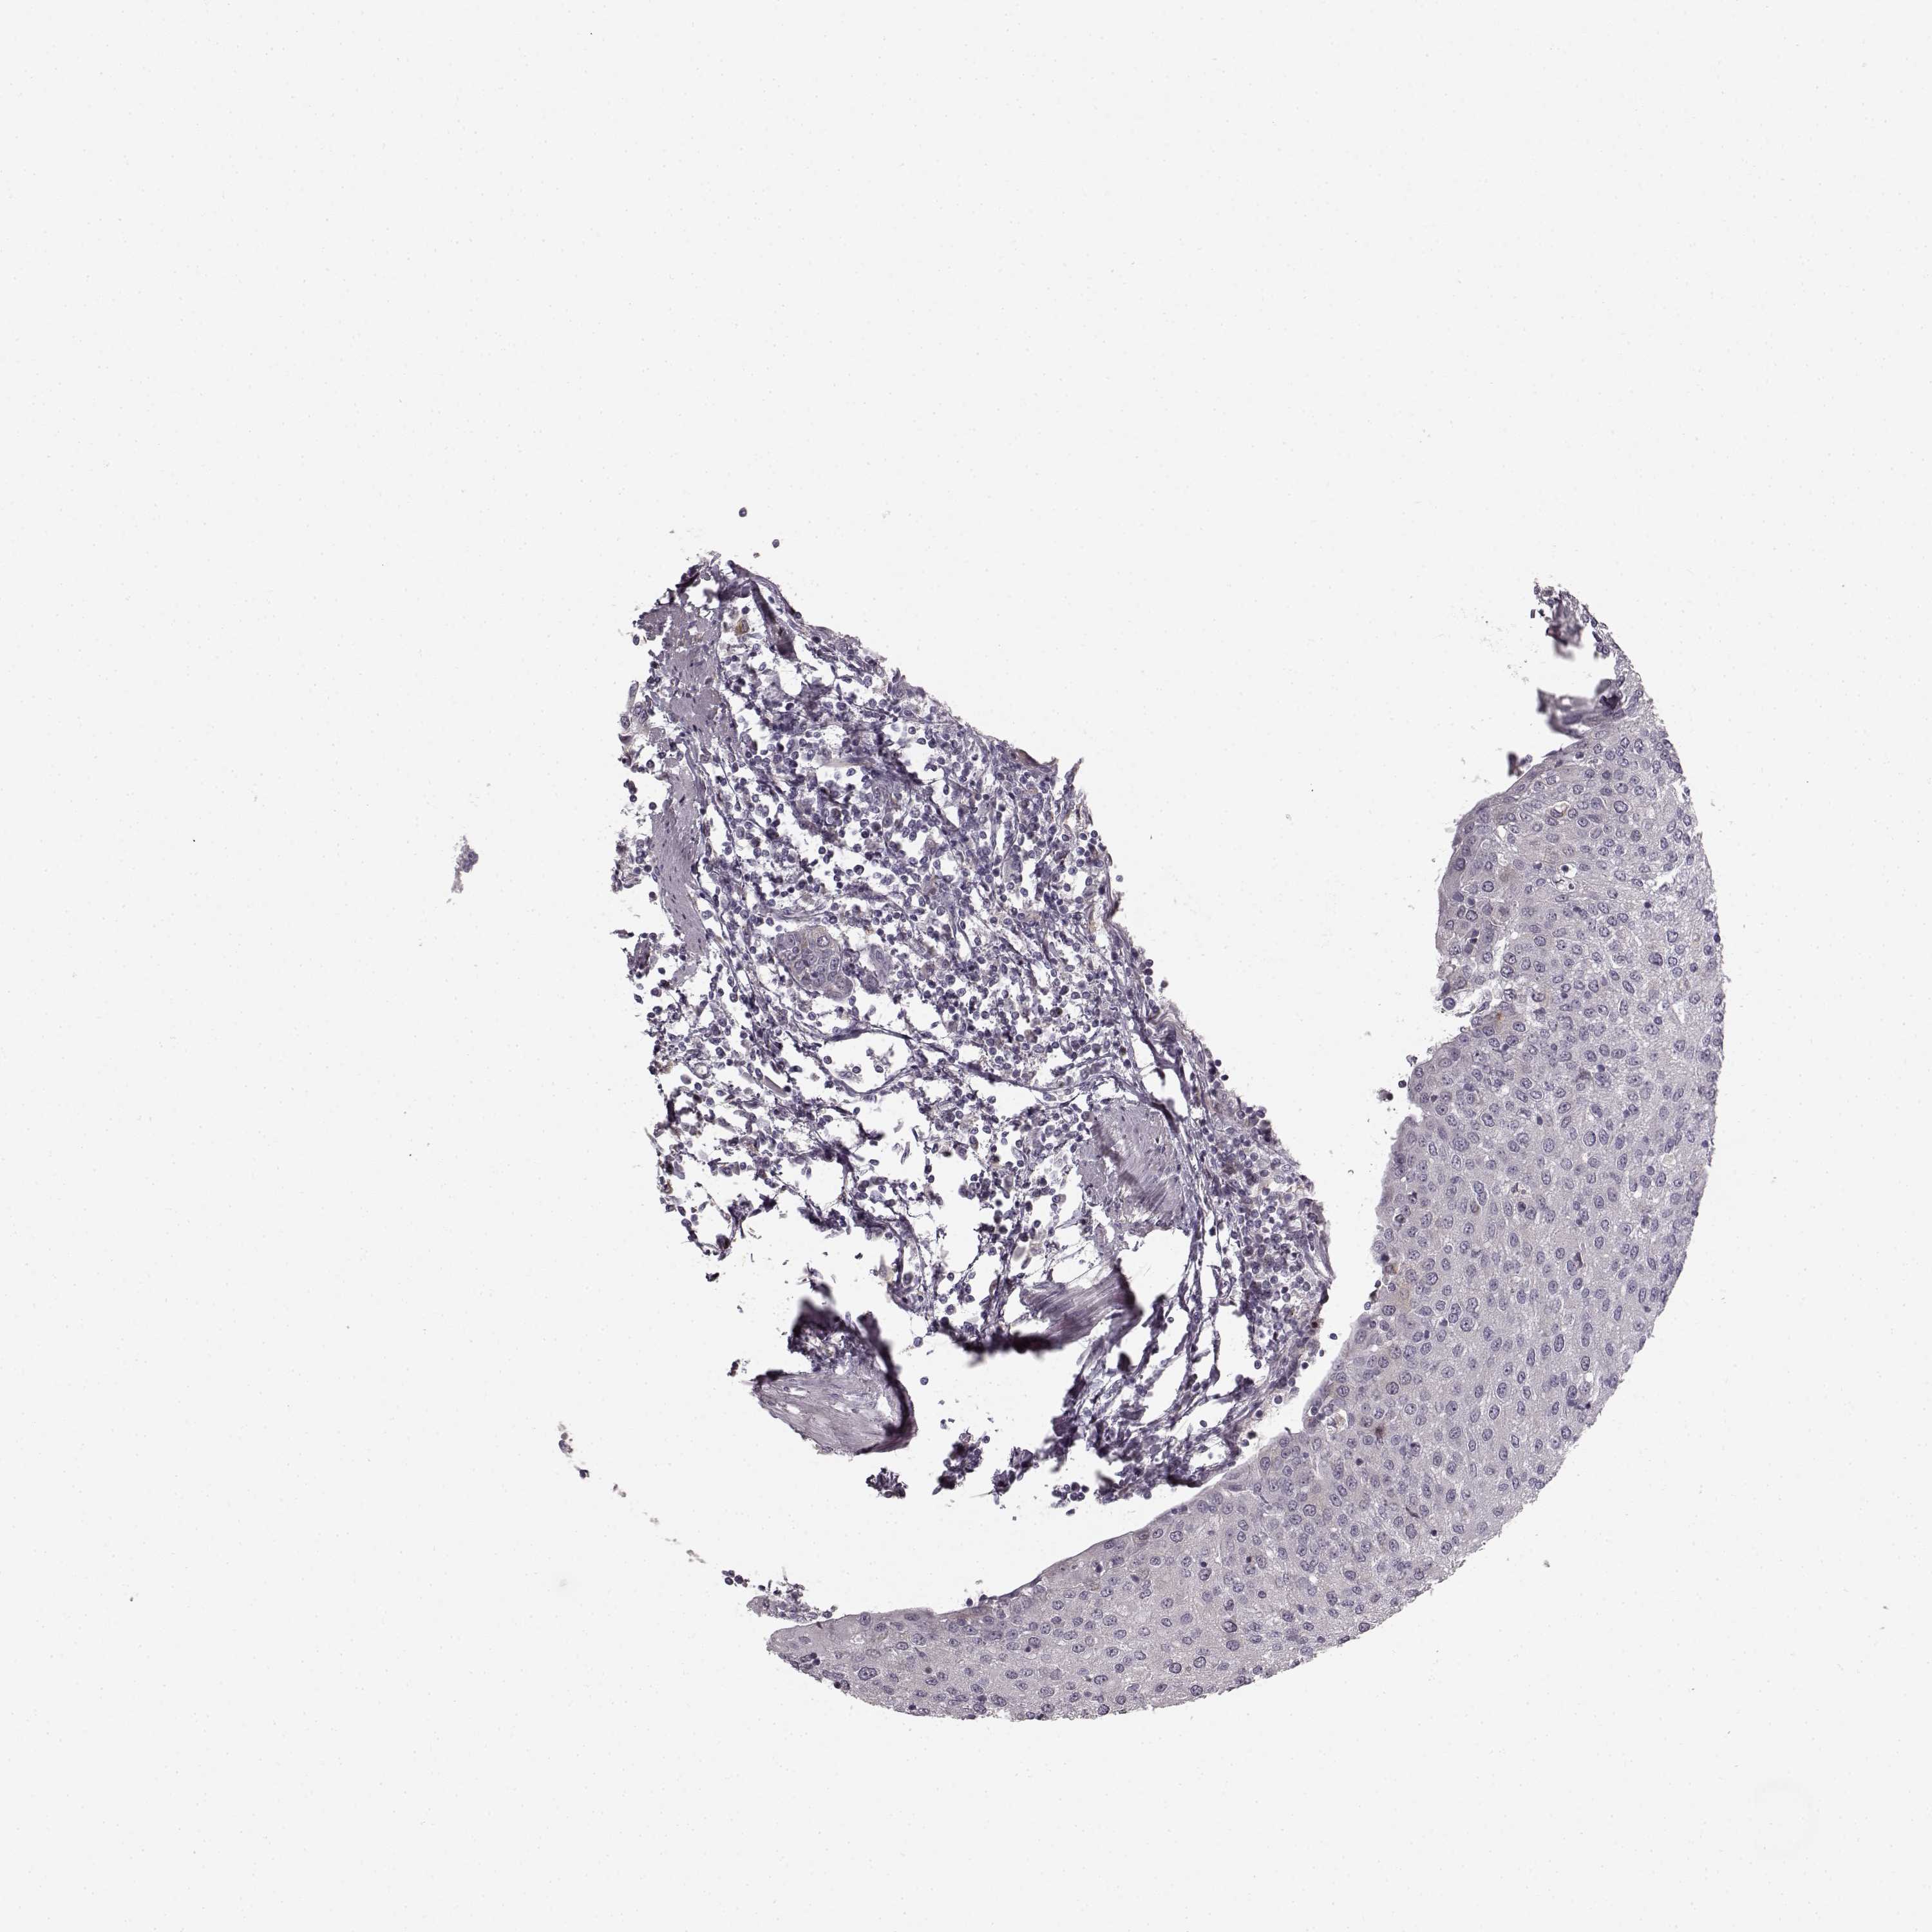

UROTHELIAL CANCER - Protein expressioni

A mouse-over function shows sample information and annotation data. Click on an image to view it in a full screen mode. Samples can be filtered based on level of antibody staining by selecting one or several of the following categories: high, medium, low and not detected. The assay and annotation is described here.

Note that samples used for immunohistochemistry by the Human Protein Atlas do not correspond to samples in the TCGA dataset.

Antibody stainingi

Antibody staining in the annotated cell types in the current human tissue is reported as not detected, low, medium, or high, based on conventional immunohistochemistry profiling in selected tissues. This score is based on the combination of the staining intensity and fraction of stained cells.

Each image is clickable and will lead to virtual microscopy that enables deeper exploration of all samples and also displays staining intensity scores, fraction scores and subcellular localization as well as patient and tissue information for each sample.

Antibody HPA040025

Antibody CAB002433

Urothelial carcinoma, High grade

Urothelial carcinoma, NOS

Urothelial carcinoma, Low grade